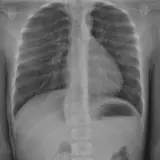

Over 2,100 interactive radiology cases, curated by radiologists for your level of training. Scroll, window, and view cases full screen — just like on PACS. Click linked findings in each writeup to jump straight to them on the image. Cases include sample reports, a focused discussion section, original illustrations, and videos.

Casos totalmente interactivos con las herramientas que esperaría de un PACS: scroll, ventana, zoom, pan, mediciones, ROI y modo de pantalla completa.

• Anotaciones enlazadas

Anotaciones extensas resaltan los hallazgos clave directamente sobre los casos. Haga clic en los hallazgos enlazados dentro de la descripción del caso para saltar a su ubicación exacta en el estudio.

Aprenda con eficiencia gracias a hallazgos de imagen anotados e ilustraciones